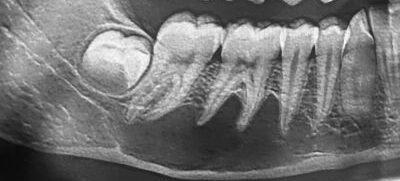

A 9-year-old girl presented to the oral surgeon, referred by her family dentist, because of a lesion in the right posterior maxilla.

A 29-year-old woman was referred to the oral surgeon by her dentist because of a radiopaque lesion in the posterior right mandible.

A 15-year-old girl was referred to the oral surgeon by her family dentist because of an unusual lesion in her posterior right maxilla.